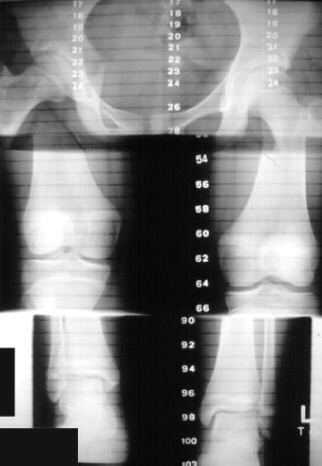

The patient demonstrated a large pigmented lesion with irregular border located in the right upper back. There was a two centimeter leg length discrepancy by the block test. X-rays showed an expansile radiolucent area with a ground glass density involving the right proximal femur . There was a healing transverse subtrochanteric fracture involving the lateral cortex . There was also an expansile lesion noted in the midshaft of the right fibula . A scanogram revealed a 1. 8 cm leg length discrepancy with right leg shorter than left . Bone age was 14 years old ( 4 years advanced) .

RADIOGRAPHIC:

Fibrous dysplasia is an intramedullary diaphyseal /metaphyseal lesion that blends with a thinned, slightly bulged cortex. The cortex of the affected bone may be thinned by endosteal erosion which creates a scalloped pattern. In long bones, the lesions are usually metaphyseal in location, extending into the rnid-diaphysis. The lesion has a homogenesis density @g it a so-called "ground glass" appearance. An angular deformity in the bone is often present at the level of the lesion. Periosteal reaction is absent except when a pathologic fracture is present. Bone scans show increased uptake-can assess the extent and multiplicity of involvement. CT scan is helpful in differentiating eosinophilic granuloma, osteomyelitis, and unicameral bone cyst. These show lower Hounsfield units (O to 40), compared to fibrous dysplasia (70 to 130). Few studies other than plain X-rays are required in a typical case of polyostotic disease.